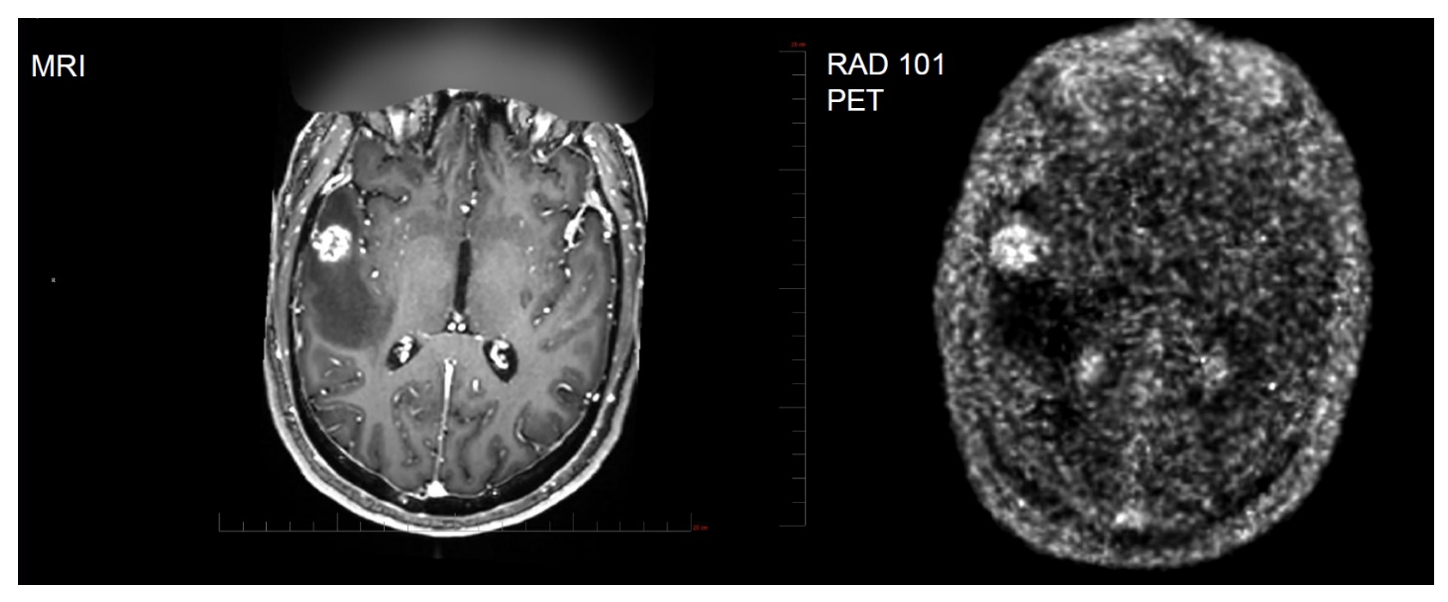

Interim results from the trial found that there was high uptake of F-18 pivalate, independent of primary tumor origin (lung, breast, melanoma and colorectal) observed in multiple brain tissues. Patients with high uptake suffered shorter overall survival (OS) (median 4 vs. 15 months with a p value of 0.0136) while MRI was uninformative. High uptake was considered to be a maximum PET Standardized Uptake Value (SUV)MAX ≥ 2.0. As an example, the following image shows agreement between the MRI scan and the PET scan. Note the bright area on the left side of each image along the horizontal centerline.

Exhibit II – Concordance Between MRI & PET

Source: Radiopharm Theranostics December 2025 Presentation

In the presentation, Dr. Kulkarni reviewed patients’ MRI and Positron Emission Tomography (PET) scan tracer uptake. While reviewing sequential images, he noted that the MRI results were inconclusive; however, the RAD101 PET scan distinctly indicated active tumor. Another subject generated MRI images that were faint and inconclusive; however, when the PET with RAD101 was examined, the tumor region was very bright and easy to distinguish.

Dr. Kulkarni further noted that the PET scans can help quantify tumor volume. Monitoring tumor size enables the oncologist to determine if the treatment is working. The presenters also differentiated between MRI and PET noting that MRI is only an anatomical picture of the brain whereas PET can show metabolic and molecular features.